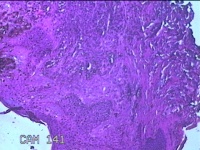

后颈部结节

性别

女

年龄

25岁

临床诊断

皮下结节

一般病史

发现后颈部“黑痣”20余年,伴近日局部瘙痒不适。

标本名称

大体所见

灰白粉红色带皮肤结节0.8x0.7x0.3cm一个,表面糜烂,切开结节呈实性,切面灰白粉红色,质软。

皮内痣